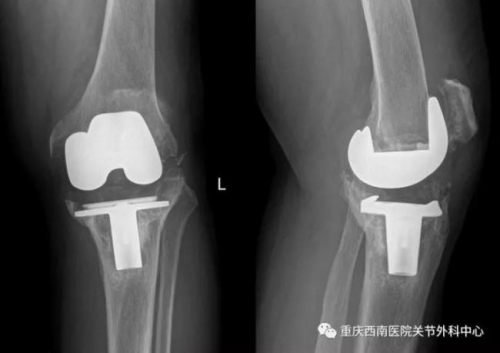

The X film before operation. [Photo: WeChat]

In the first surgery of its kind worldwide, an 84-year-old Chinese man has received knee surgery using 3D printing technology to fill large bone defects with tantalum, a rare metal, at a hospital in Chongqing Municipality, reported cqnews.net.

Porous tantalum has been developed to solve the technical problem. Tantalum pads are individually designed for patients by computer-aided design and precise 3D-printing technology.

The surgery is greatly simplified, avoiding many possible risks. Mr. Zhang, who received the knee surgery was able to complete some basic movements on the first day after his surgery and is expected to leave the hospital in just four to five days.